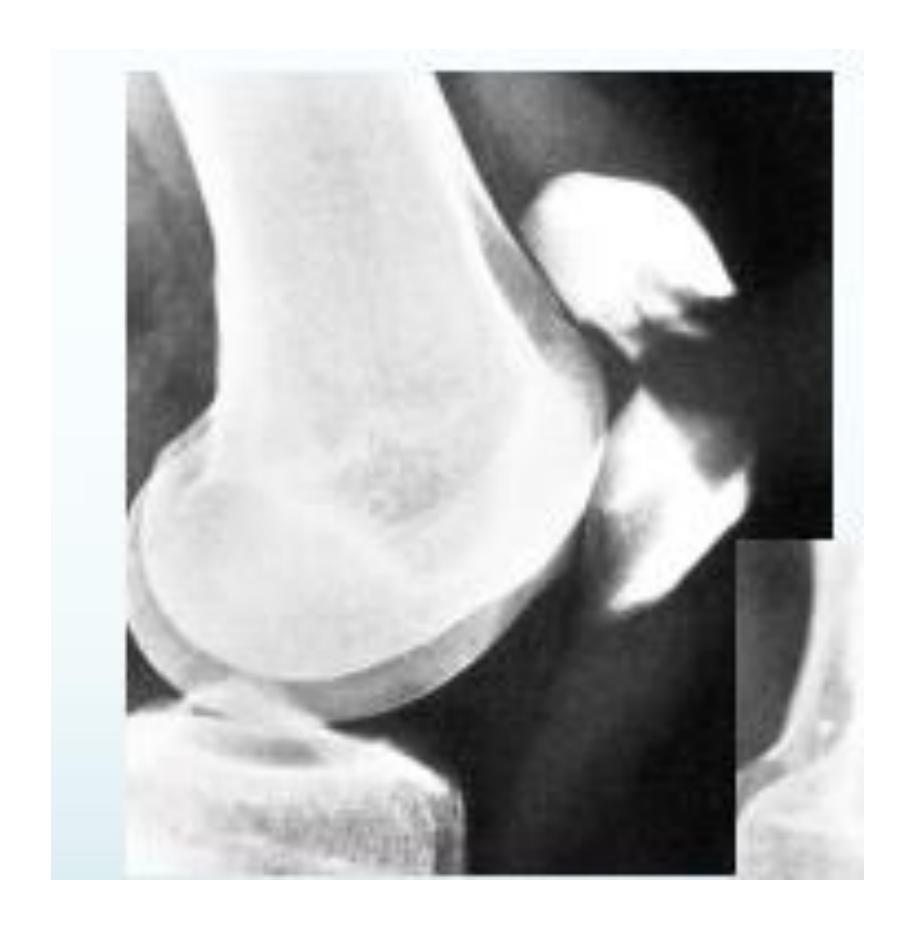

Tibial Plateau Fracture

Diagnosis: Tibial Plateau fracture Characteristics: Intra-articular Treatment: ORIF CT scan is necessary for evaluation